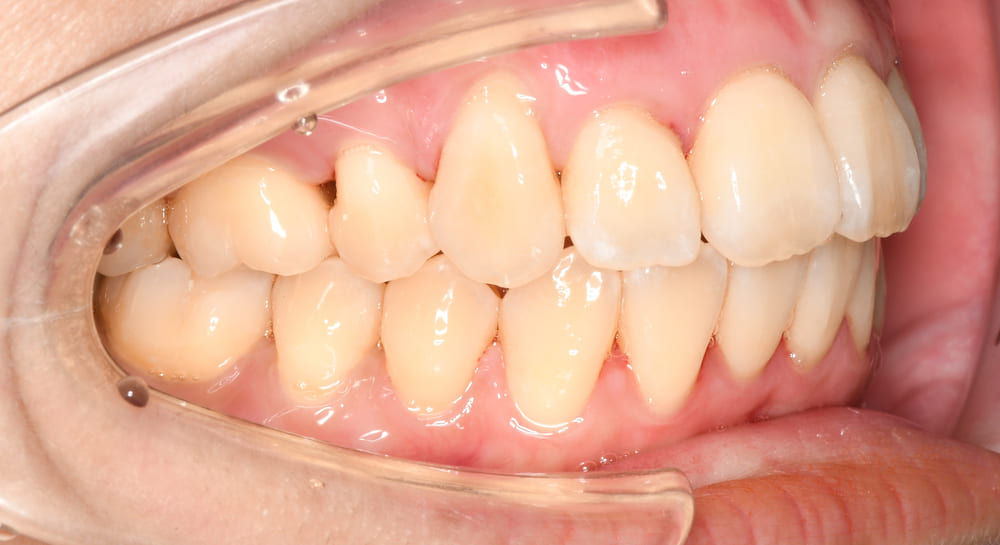

右側の写真では、

という、典型的な開咬パターンが確認されました。